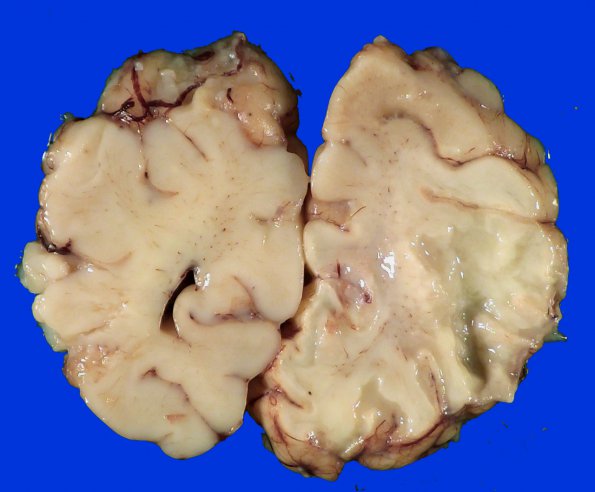

This large infarct involves the territory of the MCA and PCA.